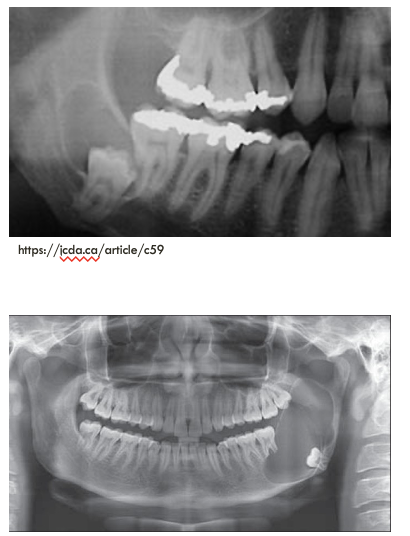

what is this

1) explain clinical

2) explain radiographic presentation

3) explain histopathology

4) explain cyst content

5) treatment